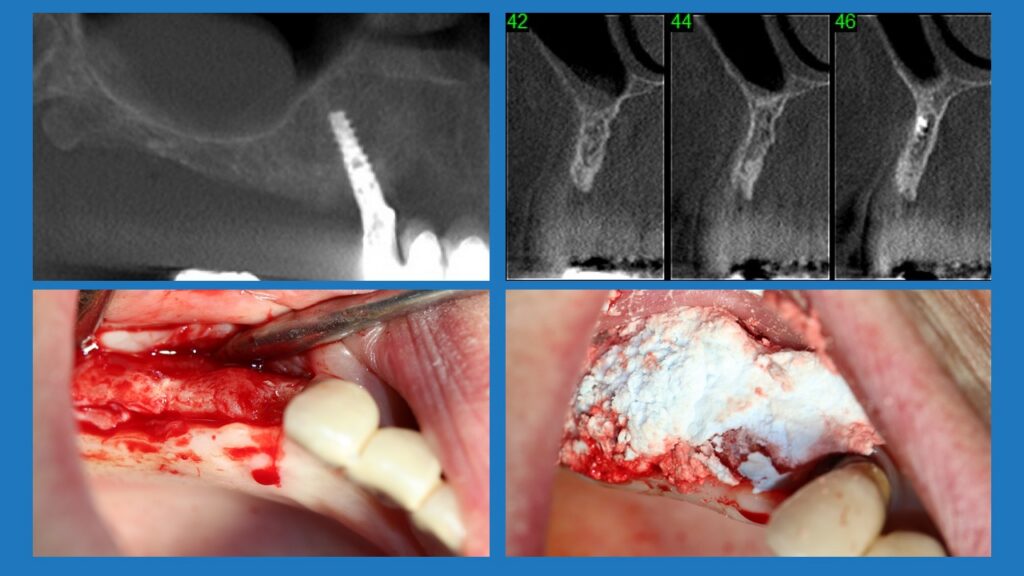

Patient in her sixties come for implant treatment in the maxilla on the right side. The ridge was very thin, about 2 mm. A lateral augmentation to thicken the ridge with Bond Apatite was performed. The implant in tooth #13 (6) is of 3 mm in diameter, the other implants #14 (5), #15 (4) and #17 (2) are of 3.75 mm in diameter. The use of the Bond Apatite in the case makes it a simple surgery, without a membrane, and with minimally invasive protocols.